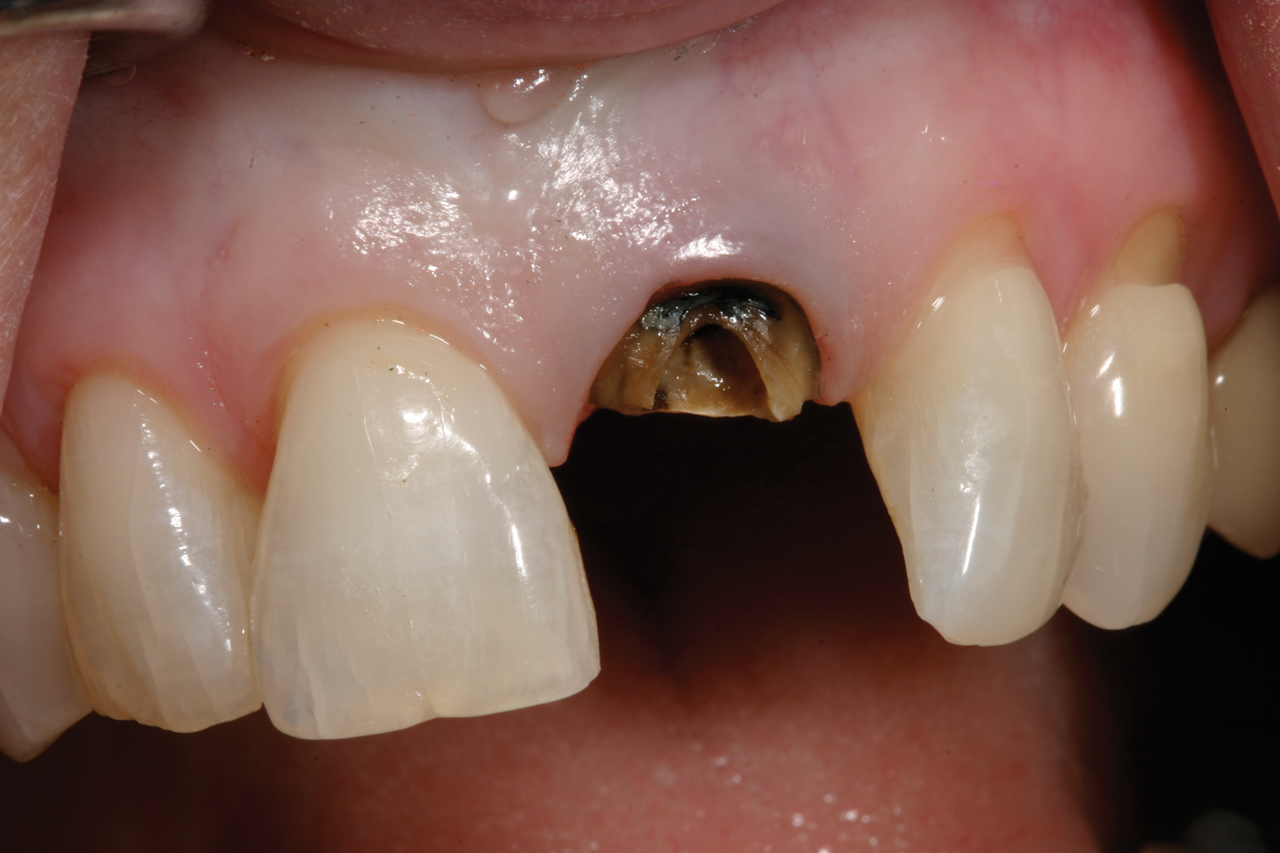

Fig 1. Badly damaged endodontically treated maxillary anterior tooth.

Figure 1

In the case presented in Figure 1 and Figure 2, the author based the decision to restore a badly compromised maxillary central incisor on his clinical experience and the patient's desire to keep the tooth, and while the restoration lasted several years, the esthetic result turned out to be poor due to the gray show-through at the gingival area and deep below the tissue from the root (Figure 2). The literature has indicated that this dark discoloration may be due to the use of certain intracanal medicaments during the root canal procedures, including some antibiotic pastes and/or liquids, or possibly the previous use of metallic restorative material in the canal.7,8 Removal of this discoloration is difficult and Zimmerli et al showed in a literature review that different bleaching techniques offer limited success and a high incidence of the discoloration returning.9

There are two important points that can be gleaned from this case when considering the restoration of compromised teeth. The first is whether the esthetic failure caused by the gray show-through could have been avoided if the tooth had been replaced with a dental implant. If the darkness was caused by the discolored root, the better option may have been to extract the tooth and graft the site; with thickened tissue and adequate bone, an implant may have been able to have been placed without any residual dark show-through. And secondly, how much should patients' desires influence, or even dictate, treatment options? While these questions may never be definitively answered, there are several criteria based on sound research that are crucial in a clinician's decision-making process.